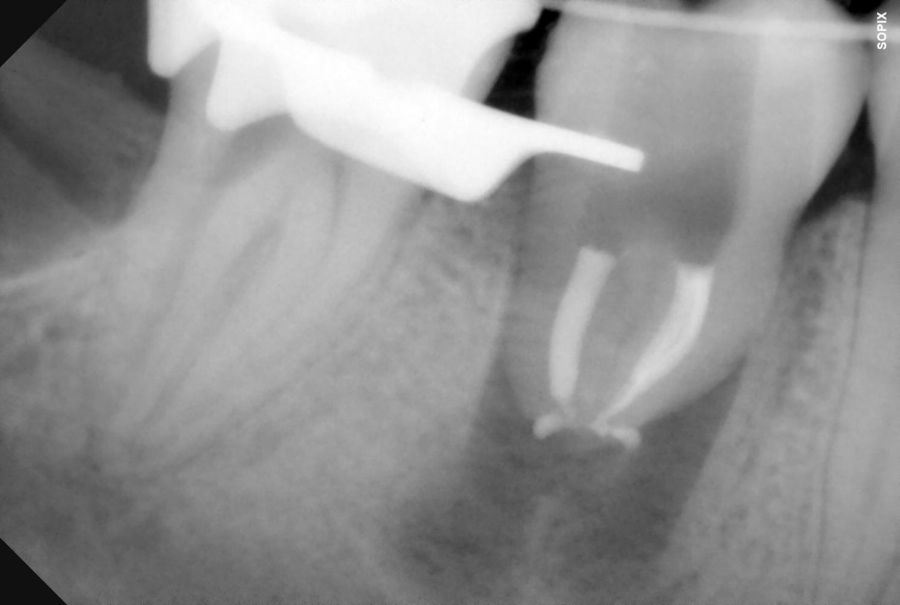

El diente donante ideal debería tener una anatomía radicular de fácil instrumentación endodóntica, y ápice abierto de al menos 1,5mm de diámetro para permitir una adecuada revascularización, con formación radicular de al menos 2/3. Así mismo, debería ser lo suficientemente pequeño para el asentamiento adecuado en el alveolo receptor, cónico, cuya extracción se pueda realizar de forma atraumática3,5,7.

El sitio receptor debe garantizar la adaptación del diente donante, se realizará un diagnóstico mediante planificación con CBCT que permita segmentar virtualmente el diente donante y llevarlo digitalmente al sitio receptor3.

La confección de la réplica 3D del diente se ha de realizar con material biocompatible y esterilizable mediante radiación gamma y beta. La ventaja del modelo estereolitográfico es minimizar el tiempo extraoral del diente donante, el daño al ligamento periodontal, así como poder remodelar el alveolo receptor sin usar el diente donante5,13,14.